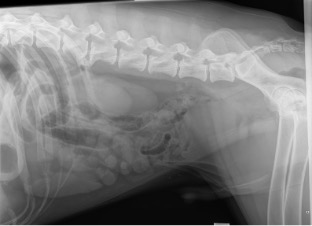

Gastric Dilation Volvulus (GDV), sometimes called bloat, is a life-threatening condition where the stomach fills with gas and twists on its axis. This leads to increased intra-gastric pressure and obstructs blood flow returning to the heart. Without emergency surgery, GDV is fatal. While the exact cause is unknown, large-breed, deep-chested dogs are at a higher risk.

A gastropexy is a surgical procedure that permanently attaches the stomach to the right side of the abdominal wall, preventing it from twisting. This eliminates the need for emergency surgery, reduces complications, and prevents death from GDV. Although a gastropexy does not prevent gas buildup, it prevents the stomach from rotating, making the condition manageable rather than life-threatening.